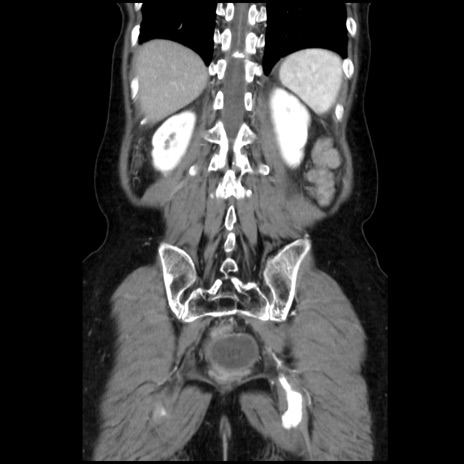

症例32(冠状断像)

【症例】40歳代 女性

【主訴】上腹部痛、嘔気・嘔吐

【現病歴】約9時間前頃から急に上腹部痛、嘔気、嘔吐が出現。改善しないため救急要請。

【既往歴】子宮頚癌(広汎子宮全摘術、放射線療法)、腸閉塞

【身体所見】腹部:平坦、軟、腸雑音亢進、上腹部を中心に腹部全体に圧痛あり。

【データ】WBC 8400、CRP 0.03